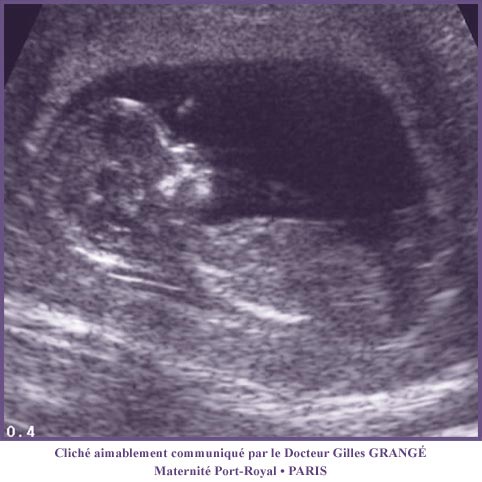

Ces anomalies pourront être décelées ultérieurement au cours de la grossesse par les examens échographiques de surveillance.

Figure 21 :Echographie pelvienne à la 12° semaine de grossesse